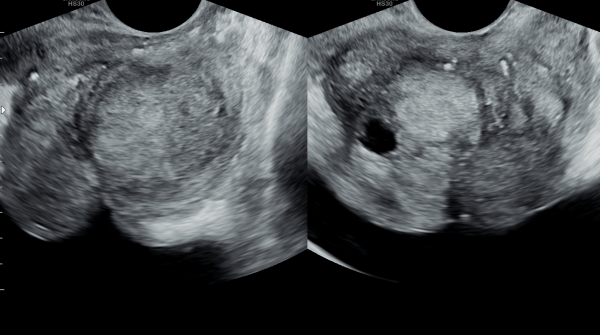

내원 당일 전립선의 정면 초음파 사진상 좌우 사정관 입구의 결석과 전립선의 이행구역에 비대해진 결절 그리고 우측 전립선 결절내 전립선 낭종이 관찰되며

방광쪽으로 커져 배뇨장애와 급박뇨가 심해 지고 있는 경직장 전립선 초음파 사진입니다.

This is a transrectal prostate ultrasound image taken on the day of the patient's first visit, showing stones at the openings of both ejaculatory ducts, an enlarged nodule in the transitional zone of the prostate, and a prostatic cyst within the right prostatic nodule. The prostate is enlarged toward the bladder, contributing to worsening voiding dysfunction and urgency.